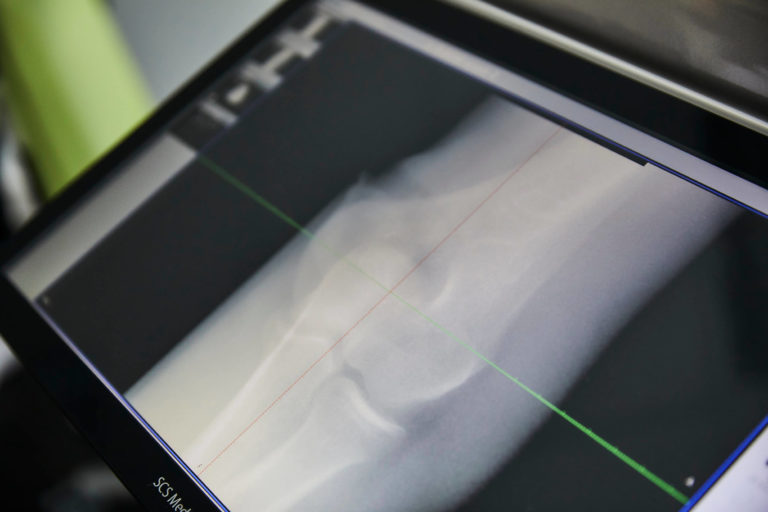

Um die Strahlungsbelastung für Sie aber so gering wie möglich zu halten, nutzen wir für Röntgenuntersuchungen die digitale Volumentomographie (DVT) und sind in Köln einer der ersten Anwender des SCS MedSeries® H22. Diese Technologie ist hochmodern und ermöglicht eine strahlungsärmere, präzise Diagnostik der Extremitäten.

Digitale Volumentomographie/DVT erkennt selbst feinste Brüche

DVT mit dem SCS MedSeries® H22 erzeugt direkt in unserer Praxis hochauflösende, dreidimensionale Bilder Ihres Körpers – und dies bei einer erstaunlich niedrigen Strahlendosis, die gerade mal ein Zehntel der Belastung von konventionellen Bildgebungssystemen mit sich bringt. Selbst feinste Brüche wie zum Beispiel an der Fußwurzel können mit dieser digitalen Volumentomographie unmittelbar vor Ort erkannt werden.